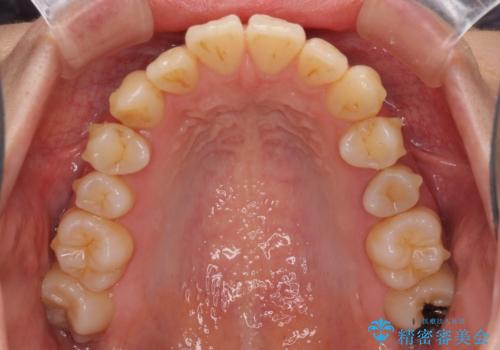

突出した印象のあった前歯をきれいに引っ込めることができたので、口が閉じやすくなり、横顔の印象をスッキリとさせることができました。

でこぼこしていて磨きにくかった歯と歯の間も清掃しやすくなり、患者様には大変満足していただきました。